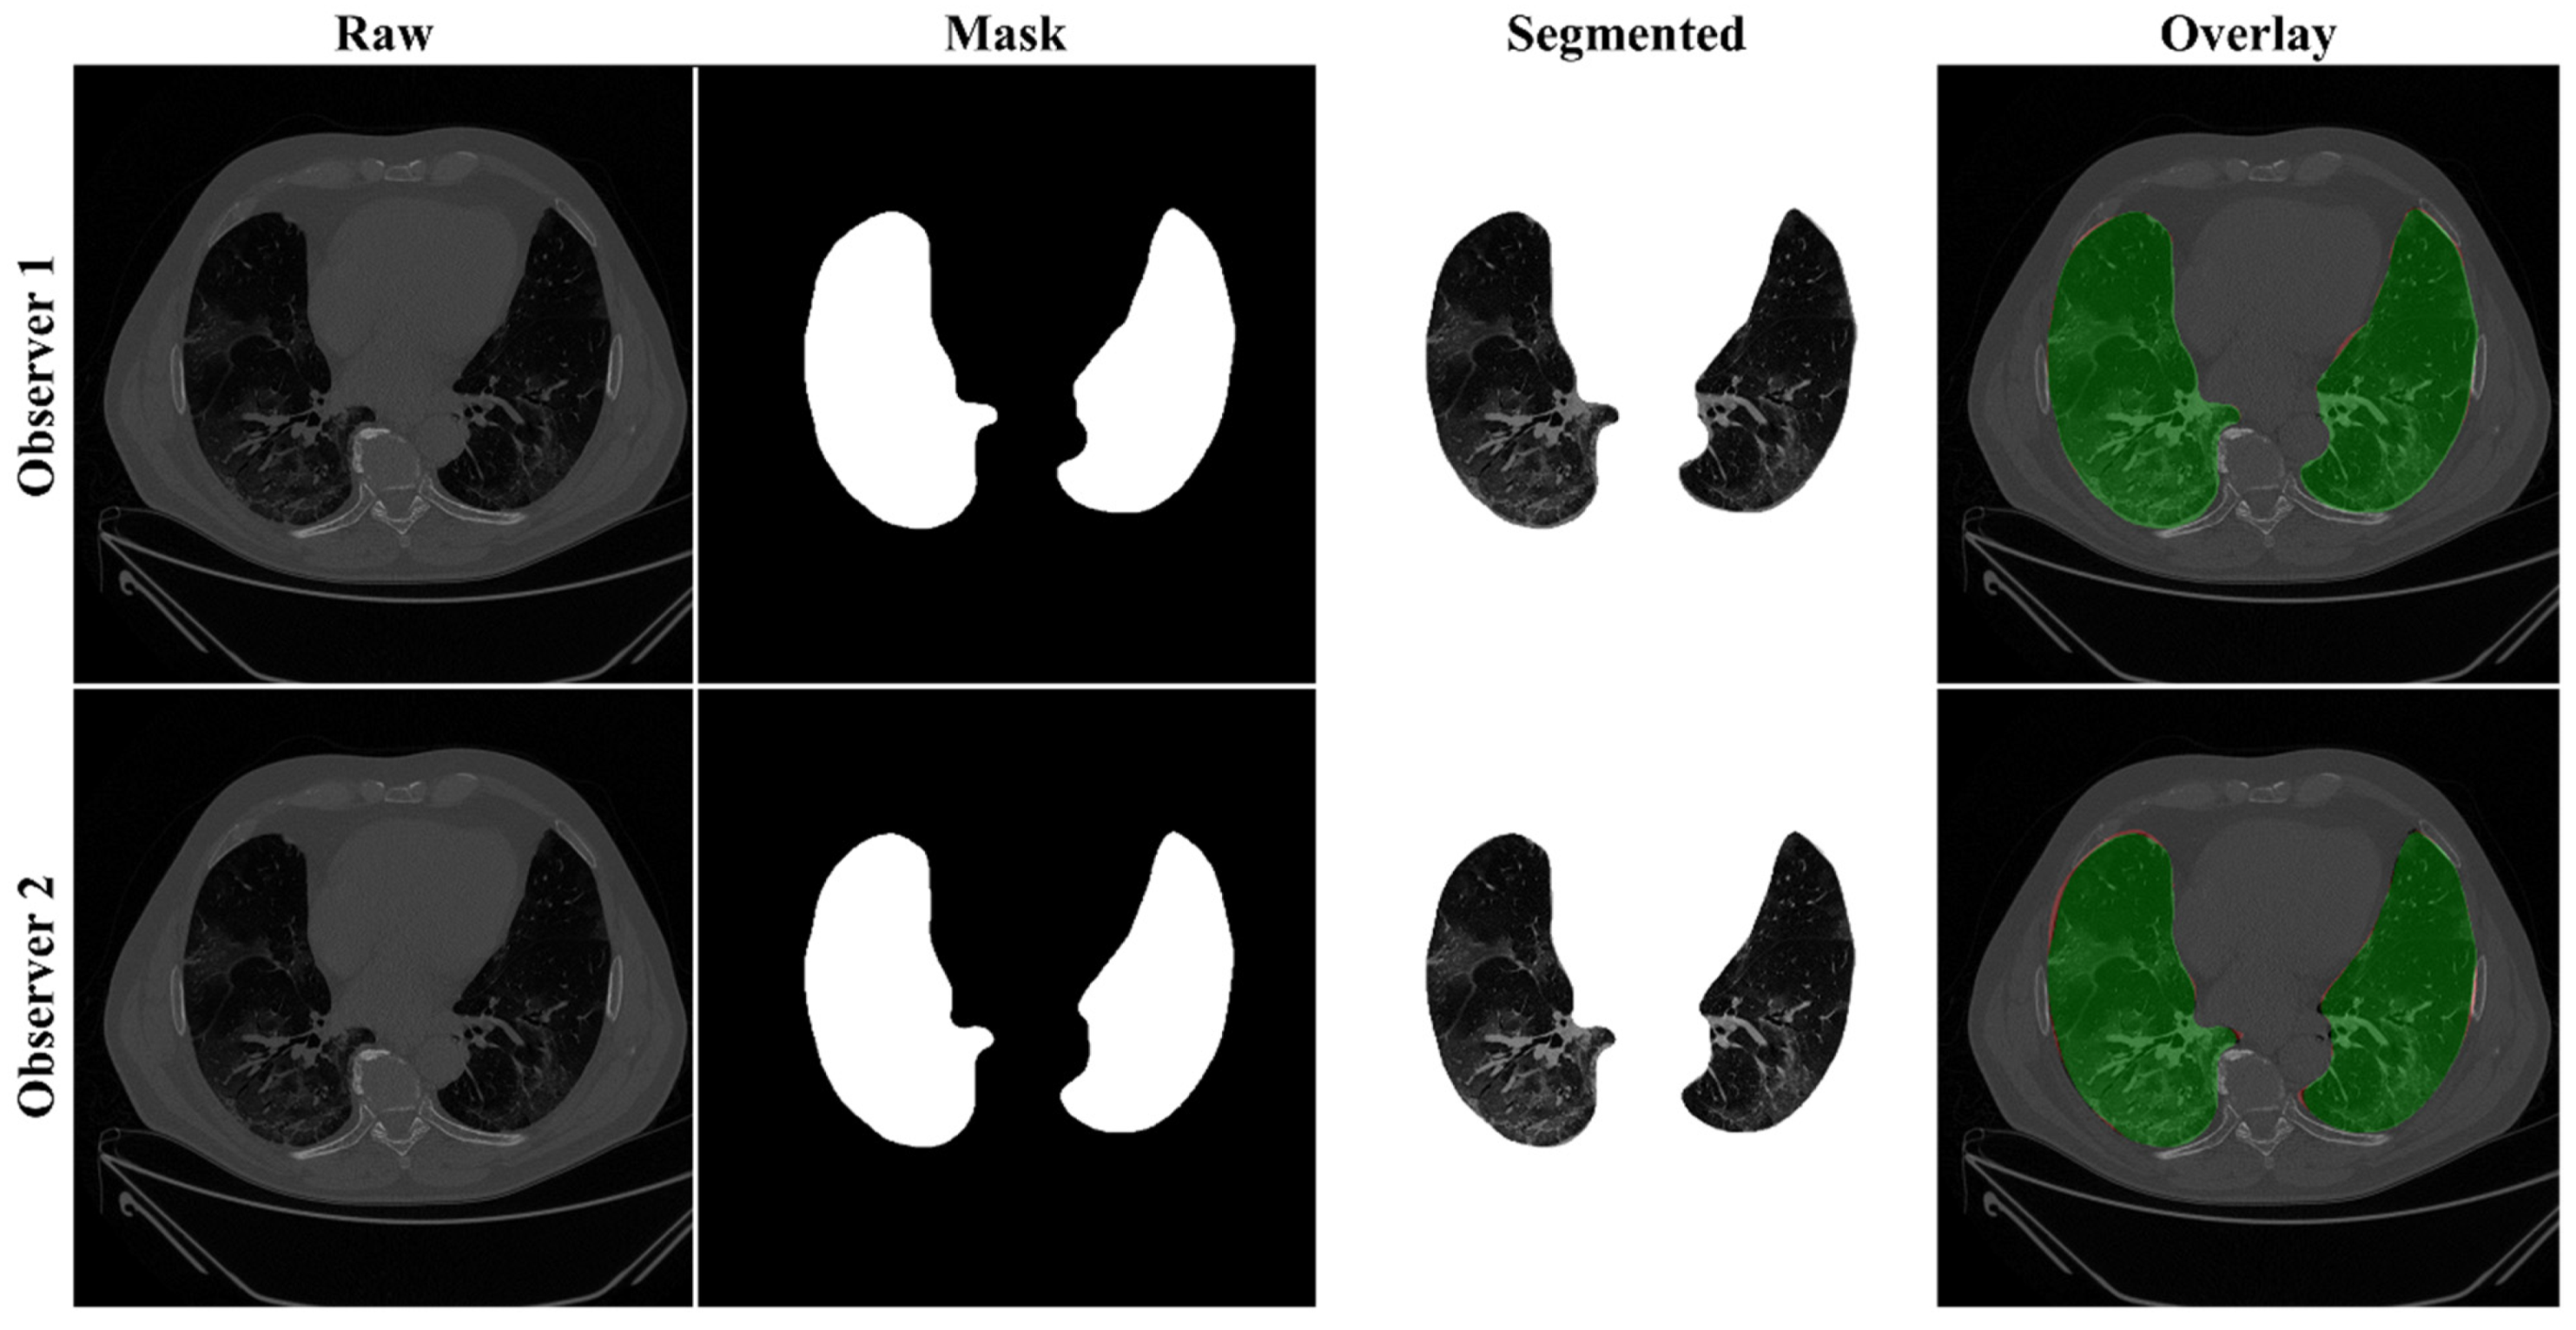

4.2.1. Lung Boundary and Long Axis Visualization